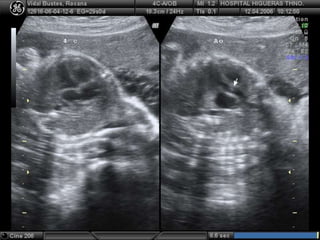

• 58.

EVALUACIÓN ANATOMÍA FETAL TORAX •CORAZÓN: parte imprescindible del examen fetal (descartar CC). 90% de las CC se dan en familias sin antec de riesgo. Lo mejor es entre 20-24 sems. inspección de forma y tamaño de parrilla costal, partes blandas de pared torácica, pulmones, corazón y diafragma

• 59.

EVALUACIÓN ANATOMÍA FETAL TORAX TÉCNICAEXAMEN CARDIACO Verificar anatomía topográfica normal de abdomen y tórax, identificar lado Dº e Iº del feto (columna, cabeza, estómago, vasos hepáticos) Visualizar 4 cámaras (transv al tórax) CORAZÓN 1/3 área torácica, eje septum 20-45º a Iº de eje AP tórax